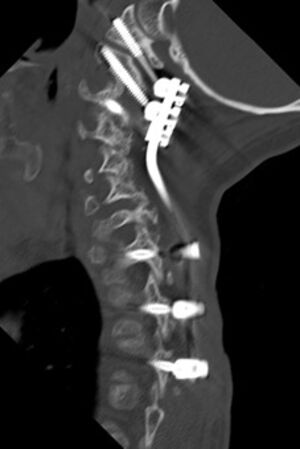

Seit 2017 führen wir unsere Stabilisierungs- und Versteifungsoperationen mit einem intraoperativen CT (s.o. AIRO©, Fa. Brainlab) durch. Diese intraoperative Computertomographie liefert direkt im Operationssaal während des Eingriffs hochauflösende Bilder von der Wirbelsäule. Zusammen mit einer Navigationssoftware wird ein dreidimensionaler Plan der entsprechenden Körperregion erzeugt. Mit Hilfe der Bildgebung können wir die notwendigen OP-Schritte plangerecht umsetzen und z.B. Implantate mit sehr hoher Präzision einsetzen. Gerade bei komplizierten Eingriffen an der Wirbelsäule hilft die neue OP-Technik, Patienten sicher und schonend zu therapieren. Die intraoperative Bildgebung, direkt im OP, erlaubt komplexe Operationen genauer und sicherer durchzuführen und dem Operateur noch während der Operation das Ergebnis zu überprüfen und bei Bedarf zu optimieren. Belastende Folgeoperationen sind so deutlich seltener und die Behandlungsqualität und Sicherheit für Patienten dadurch erheblich verbessert.